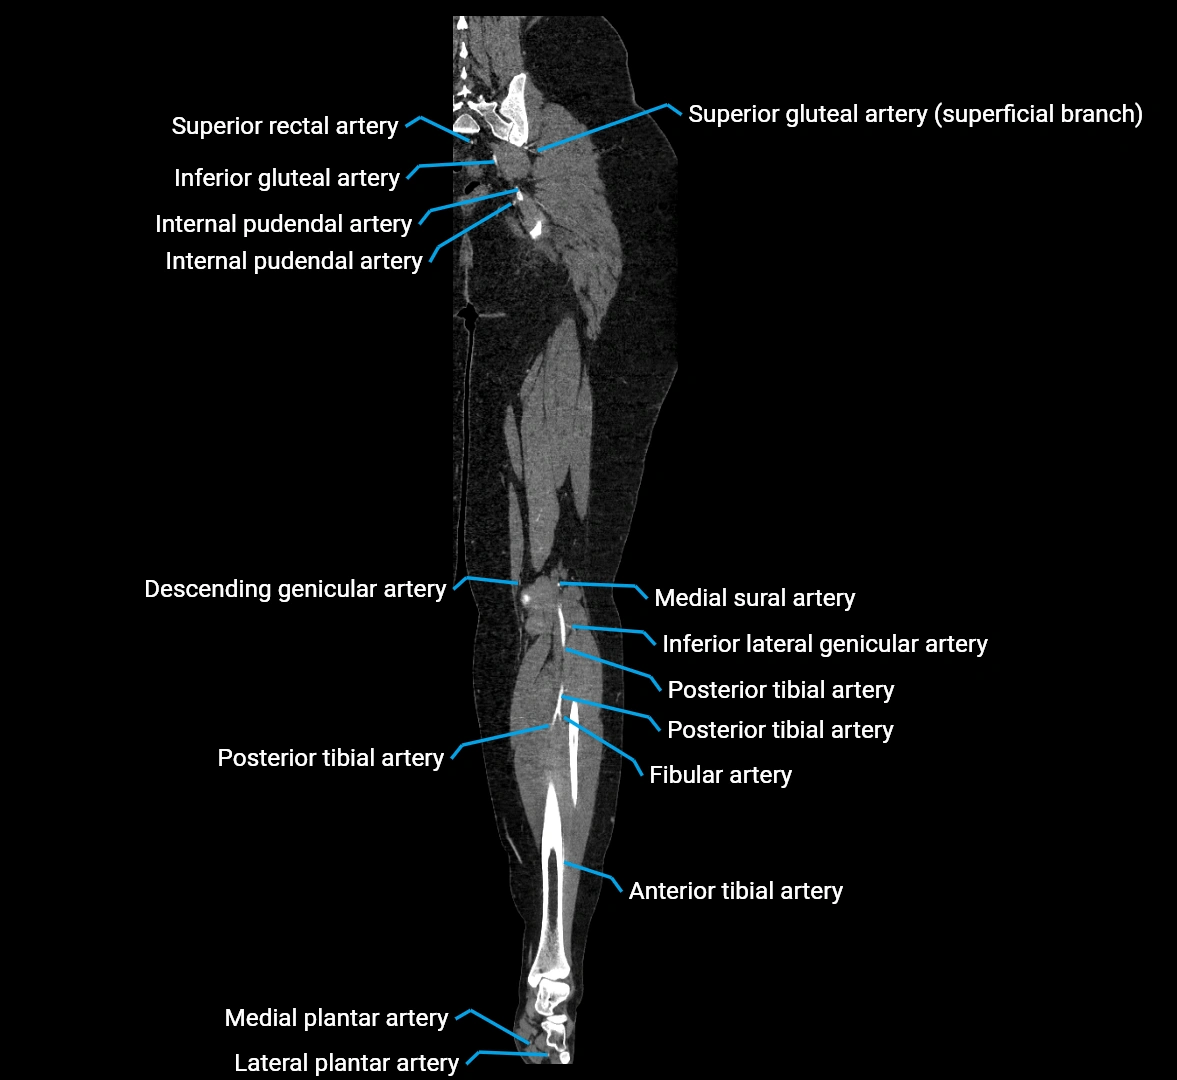

Contrast-enhanced CT (CTA):

• Gold standard for abdominal aortic imaging

• Provides excellent detail of lumen, wall, aneurysm, thrombus, and branch vessels

• Multiplanar and 3D reconstructions help in aneurysm measurement, stent graft planning, and dissection evaluation

• Detects acute rupture, traumatic injury, or occlusion with high sensitivity